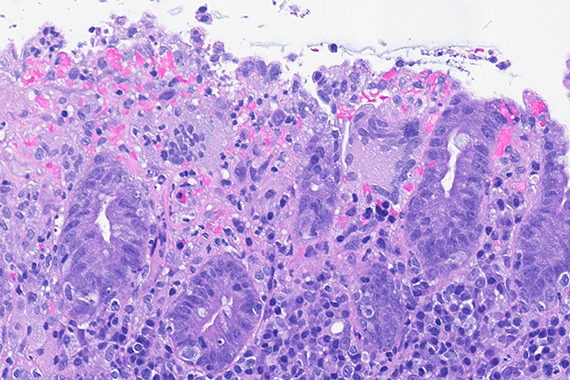

Colon biopsies in a 87 year-old female with chronic watery diarrhea.

Collagenous colitis with giant cells.

An 87-year-old woman presented with chronic, non-bloody, watery diarrhea and underwent colonoscopy, which revealed no endoscopic abnormalities. Biopsies were taken.

Histology of several colonic sites showed a thickened subepithelial collagen band (>10 μm), predominantly beneath the superficial epithelium but also surrounding the crypts (Panel A). Surface epithelial injury was also observed, with focal mucin depletion and detachment of superficial epithelial cells (Panel B). Lamina propria showed increased cellularity, with lymphocytic and plasmocytic infiltration, along with numerous giant cells (Panel C). There was no crypt architectural distortion. The collagen deposition was highlighted by Masson’s trichrome stain (Panel D) and strongly by tenascin immunohistochemistry (Panel E).